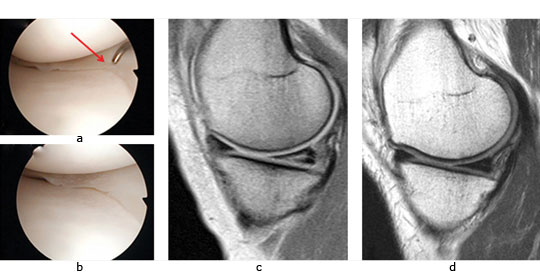

A similar approach can be used in combined chondral injuries and meniscal tears. Figure 2 shows the arthroscopic fi ndings of a 61-year-old orthopaedic surgeon and recreational skier. Two years following injury and after an unsuccessful arthroscopic debridement he was troubled by a persistent knee effusion, limited walking distance and lateral patellar maltracking with chondral lesions over the lateral patellofemoral joint. There was also an associated degenerated lateral meniscus and chondral injury in the lateral compartment. The patient underwent arthroscopic subchondral drilling together with lateral patellar release and subsequently received stem cell therapy. MRI scans at five months showed evidence of repair and regeneration accompanied with clinical improvement.

Fig. 2 Intra-operative views following subchondral drilling with the corresponding MRI scans after surgery and progressive healing at five months of the lateral trochlear, lateral femoral condyle, lateral tibial plateau and lateral patellar facet.

Some of our early results illustrate the potential benefits of this therapy. We treated a 43-year old woman who had sustained both a chondral injury and a symptomatic large posterior horn intra-substance tear of the medial meniscus (Fig.5a). Intra-operatively her meniscus was found to be intact on the surface, and consequently we undertook needling of the posterior aspect of the medial meniscus to stimulate healing (Fig.5b). This was combined with treatment of the chondral lesion and subsequent injection of PBSC and HA. The patient was able to return to sporting activities by two years and at the time of review three years later, she was running three times per week. An MRI scan taken after three years demonstrates complete healing of the meniscal lesion (Fig.5d). A case report such as this does not provide irrefutable evidence that the meniscal healing was due to the PBSC, however, conventional wisdom tells us healing of such a lesion would not normally be expected after needling alone.

Fig. 5 A 43-year-old woman presented with a chondral injury of her left knee accompanied by symptomatic intra-substance tear of the medial meniscus.

Figure 5a – intra-operative view of the posterior aspect of the medial meniscus showing intact surfaces.

Figure 5b – arthroscopic view after multiple needling into the posterior aspect of the medial meniscus.

Figure 5c – pre-operative MRI scan showing intra-substance tear of the posterior aspect of the medial meniscus. Figure 5d – MRI scan after three years showing complete healing of the meniscal tear.